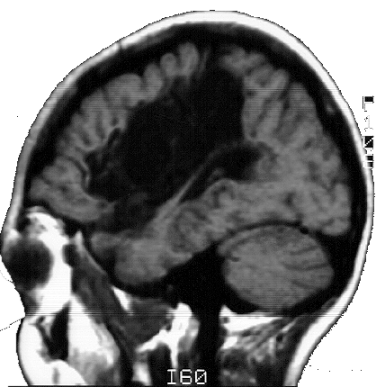

As crianças ARM e KTG são portadoras de lesões cerebrais denominadas Esquizencefalia (Fig. 5 e 6), que são decorrentes de distúrbios no processo embriogênico, que ocorrem no primeiro trimestre da gravidez. As lesões no indivíduo ARM se localizam no lobo frontal esquerdo e incluem também a ausência do septo pelúcido. Já a criança KTG tem as lesões localizadas no lobo parietal direito e também mostra sinais de comprometimento do hipocampo direito.

As lesões do indivíduo WA são do tipo Leucomalácia Multicística e se localizam principalmente no lobo parietal esquerdo. As lesões decorreram de problemas anóxicos perinatais, causados por problemas que a mãe experimentou alguns dias antes do parto. WA e ARM são canhotos e hemiplégicos à direita, e apresentaram atraso no desenvolvimento psicomotor. KTG é destra e tem hemiplegia à esquerda, apresentou também, atraso do desenvolvimento psicomotor.

Os MAREs de todos os indivíduos mostram uma atividade cerebral coerente com a lesão encontrada nas correspondentes MRIs. Assim, por exemplo, ARM tem uma lesão frontal esquerda na MRI, que está associada á um silêncio funcional nas derivações frontais esquerda nos seus MAREs (Fig. 5). Já o indivíduo WA tem uma lesão que se localiza predominantemente no lobo parietal esquerdo, que está associada a uma ausência de atividade nas derivações C3 e P3 nos seus MAREs mostrados na fig. 5. Finalmente, a lesão de KTG se localiza principalmente no lobo parietal direito, que se reflete nos correspondentes MAREs, por uma diminuição da ativação, principalmente, nas derivações P4 e T6.

Os MAREs associados ao processamento verbal no indivíduo ARM mostra uma ativação intensa nas derivações frontotemporais direitas, tanto no início como no final da apresentação da charada. Na fase inicial da apresentação do som, ocorre ativação nas derivações FZ e CZ.

Um padrão semelhante de ativação cerebral é observado também no indivíduo WA. Outra vez, o processamento do som verbal está associado a uma ativação das derivações frontoparietais direitas. Entretanto, observa-se também uma ativação em algumas derivações frontais esquerda. O fato marcante é a aparente redução da atividade nas regiões temporoparietais esquerdas.

A criança ARM tem uma lesão que compromete extensamente seu lobo frontal esquerdo, mostrando uma hemiplegia à direita e dificuldades de fonação. Sua lesão afeta também o fascículo arcuado, de modo que as áreas temporais esquerdas estão isoladas do pouco córtex frontal esquerdo que restou nesse indivíduo.

Corroborando esses achados, os MAREs apresentados na fig. 5, mostra uma boa ativação de áreas frontotemporais no hemisfério direito, quando do processamento da informação verbal no jogo de charadas. Parece, portanto, que a capacidade lingüística dessa criança é suportada pela ação do hemisfério não dominante. Aceita essa premissa, os MAREs mostrados na fig. 5 para esse indivíduo, demonstram claramente um alocação da função verbal no hemisfério direito; isto é, mostram um caso típico de plasticidade neural induzida por uma lesão congênita. Outros autores, por exemplo Graviline et al., 1998; reportam o sucesso de realocação de funções com a precocidade da lesão.

As lesões de WA comprometem fundamentalmente o lobo parietal e parte do lobo frontal esquerdos. Mais uma vez, o fascículo arcuado parece estar lesado. Outra vez, tem-se o isolamento entre o lobo temporal e as áreas frontais no hemisfério esquerdo. WA é uma criança que tem uma hemiplegia direita e dificuldades articulatórias. Entretanto, é também capaz de uma boa compreensão da linguagem falada, comprovada pelo seu bom rendimentos nos jogos de ordenação, memorização, interpretação e reconstrução. Um fato marcante em sua linguagem é a ausência do uso das palavras funcionais: artigos, preposições, etc. Esse fato está de acordo com o comprometimento córtex frontal esquerdo observado neste indivíduo (pe, Pinker, 1995; Rocha, 1999).

Os MAREs apresentados na fig. 5 para o indivíduo WA, mostram claramente uma redução da atividade nas derivações temporoparietais esquerda, compatível com a lesão estrutural observada na MRI. Uma vez mais, há um isolamento do lobo temporal em relação ao frontal, no hemisfério esquerdo. Outra vez, observa-se uma compensação desse isolamento, por um aumento do envolvimento do hemisfério direito no processamento da informação verbal.